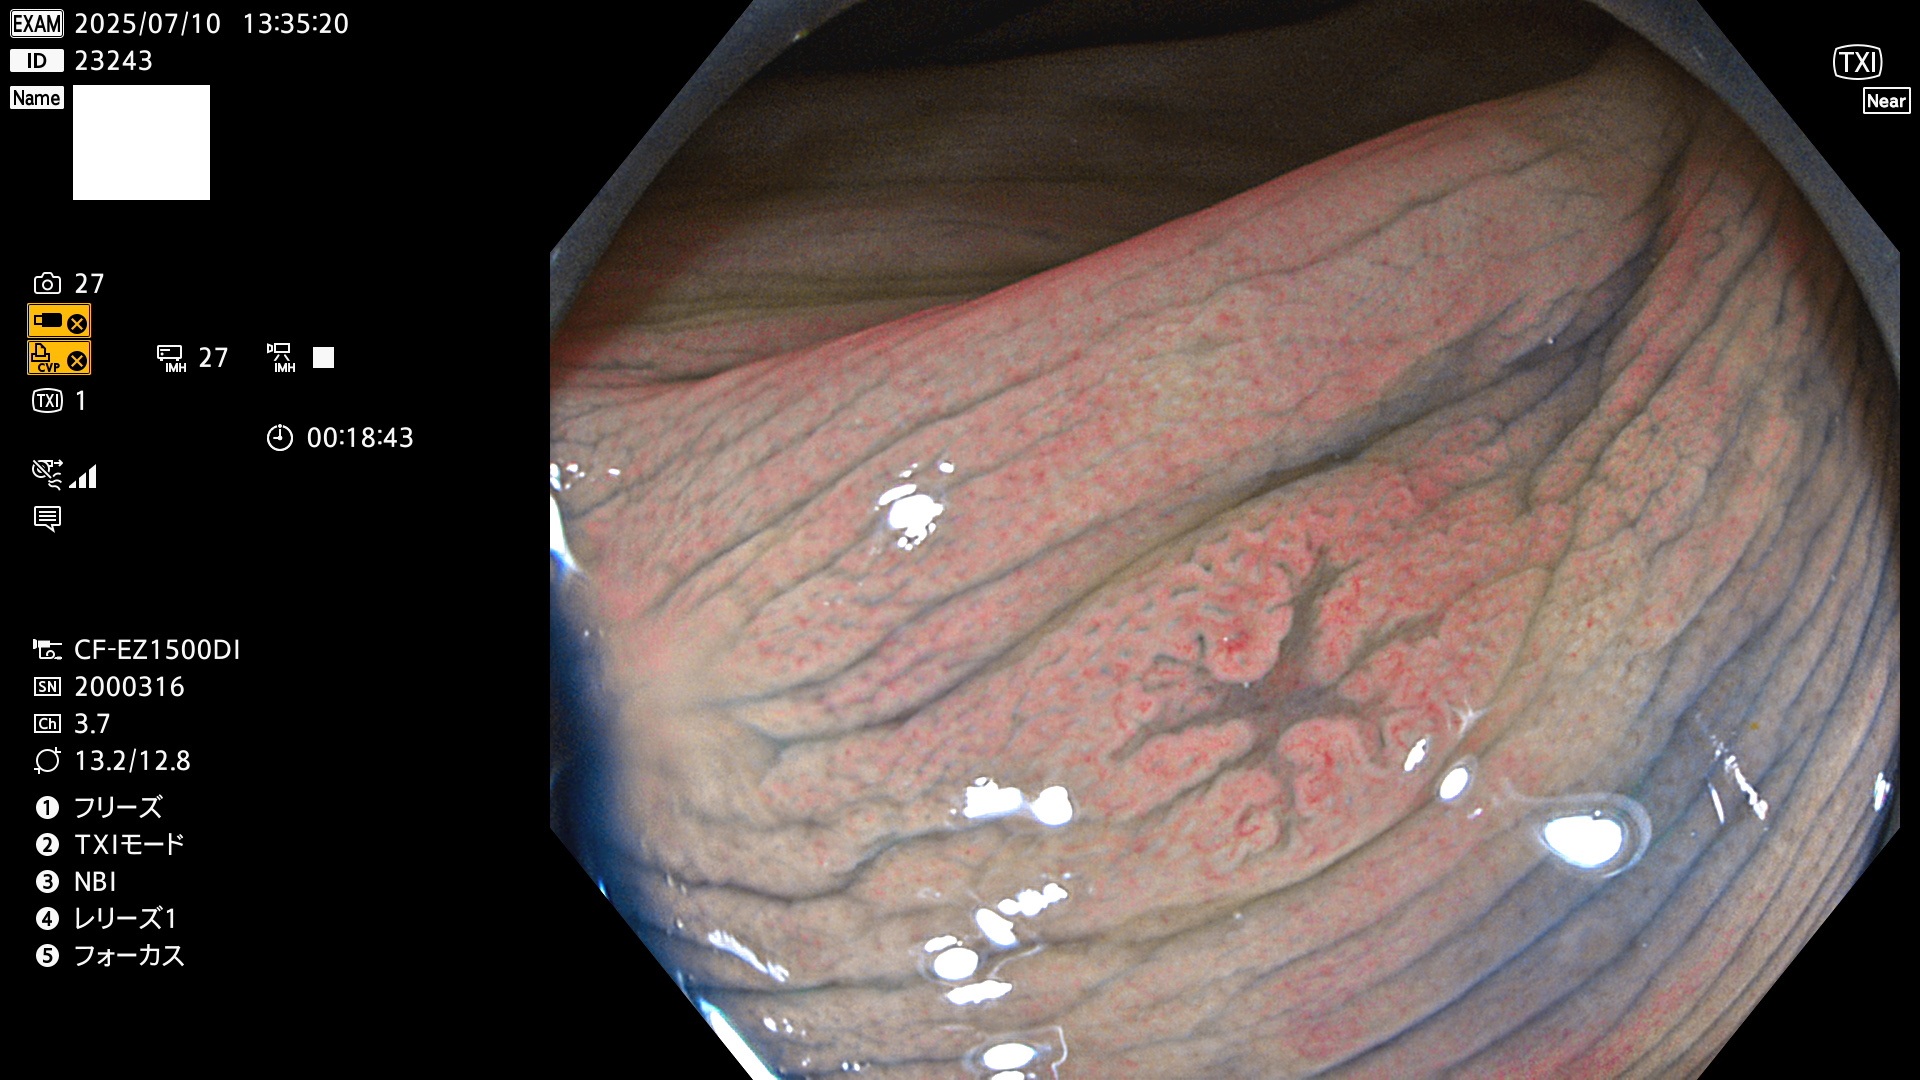

2025年7月10日〜7月13日の4日間(40件)15個 (Uc_ADR=15/40=38%)